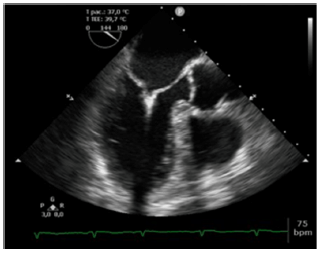

Analise a figura a seguir.

Assinale a opção que indica o nome do dispositivo protético presente na foto acima.